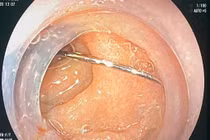

(khoahocdoisong.vn) - Khoa ngoại tổng hợp - Bệnh viện Nhi trung ương vừa tiếp nhận và phẫu thuật thành công gắp dị vật cho bé P.D.C. (3 tuổi), bị kim đâm xuyên thành ngực.